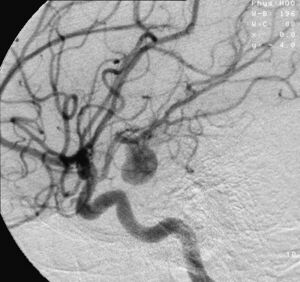

image الإنجليزية

Aneurysem.jpg

٥٢٠ × ٤٨٨؛ ١١٦ كيلوبايت

media legend الإنجليزية

Angiography of an aneurysm in a brain artery. The aneurysm is the large bulge in the center of the image. (الإنجليزية)